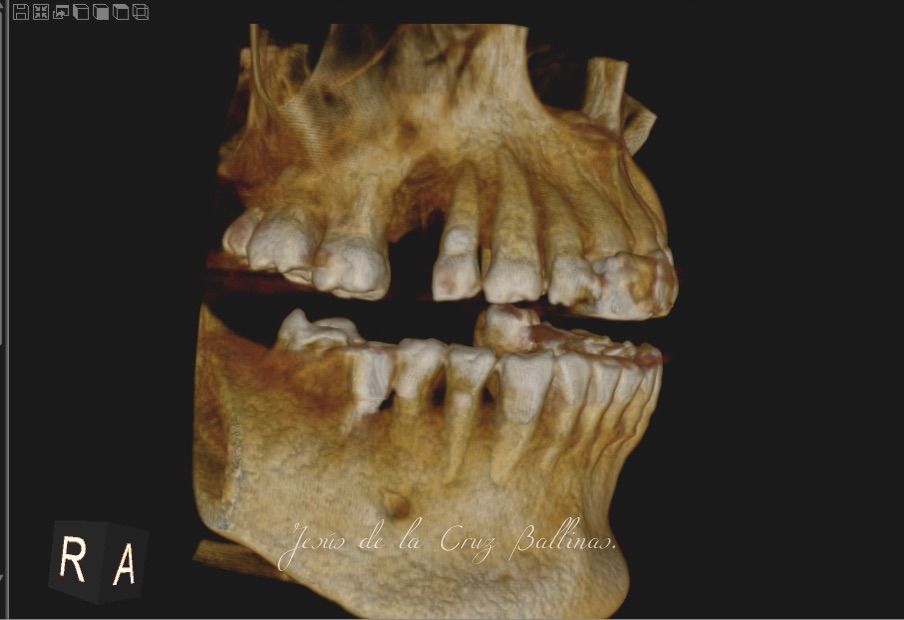

Especialista en Implantología Oral quirúrgica y protesica, cédula de especialidad: 12411844

La especialidad en Implantología Oral se enfoca en sustituir órganos dentarios perdidos por implantes dentales mediante una fase quirúrgica y una fase protesica y de esta manera devolver la función, estetica y confort dental del paciente.